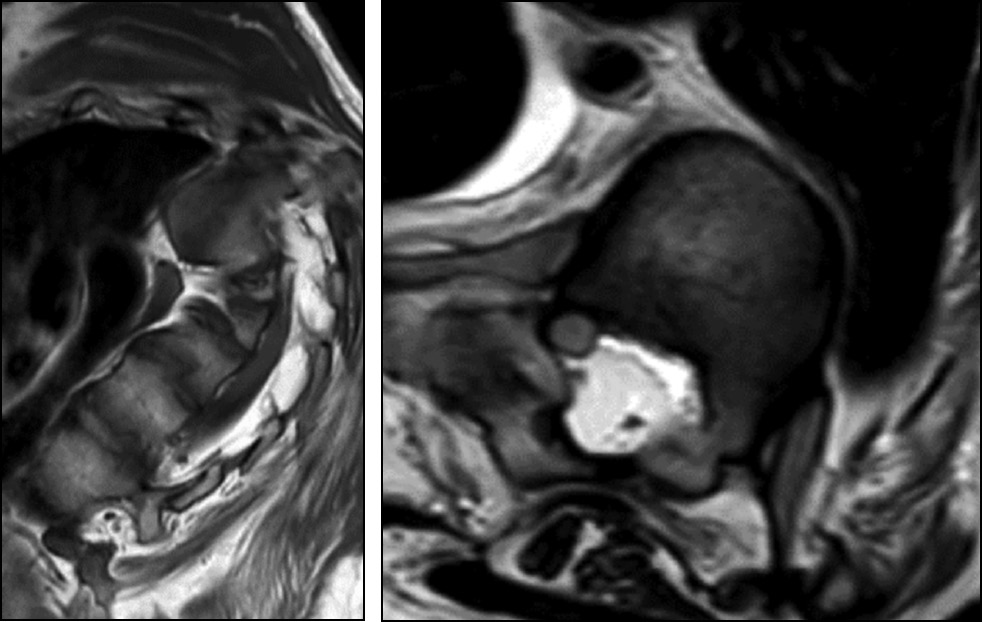

Пациенту проведено обследование: спиральная компьютерная томография (СКТ), СКТ-миелография и МРТ грудопоясничного отдела позвоночника. По данным МРТ, на уровне Th5–Th7 позвоночный канал заполнен жировой тканью, спинной мозг смещён вправо, ликворное пространство на этом уровне не прослеживается, признаки миелопатии не определяются (рис. 8).

Рис. 8. Магнитно-резонансная томография грудного отдела позвоночника на вершине деформации.

Fig. 8. Magnetic resonance imaging of the thoracic spine at the apex of the deformity.

С учётом данных анамнеза, результатов генетического обследования, нейроортопедического статуса и результатов лучевых методов обследования установлен диагноз: наследственная невропатия Шарко–Мари–Тута, тип 4С. Нейрогенный левосторонний кифосколиоз грудного отдела позвоночника IV степени. Компрессия спинного мозга на уровне Th6–9. Нижний смешанный глубокий парапарез. Нейрогенная эквинополоварусная деформация стоп.

В связи со сложностью деформации, компрессией спинного мозга, прогрессирующим усугублением неврологического статуса решено изготовить индивидуальную анатомическую модель позвоночника и спинного мозга на основании данных проведённой КТ-миелографии (рис. 9). Модель была изготовлена с раздельной печатью костных структур и спинного мозга, а также с возможностью разбора позвоночника с креплением составных частей на магнитах, что позволило напрямую при реальном объёмно-тактильном рассмотрении выявить зону наибольшей компрессии миелорадикулярных структур на уровне Th6–9, обусловленную корнями дуг, рёберно-поперечными суставами, головками рёбер с вогнутой стороны деформации.